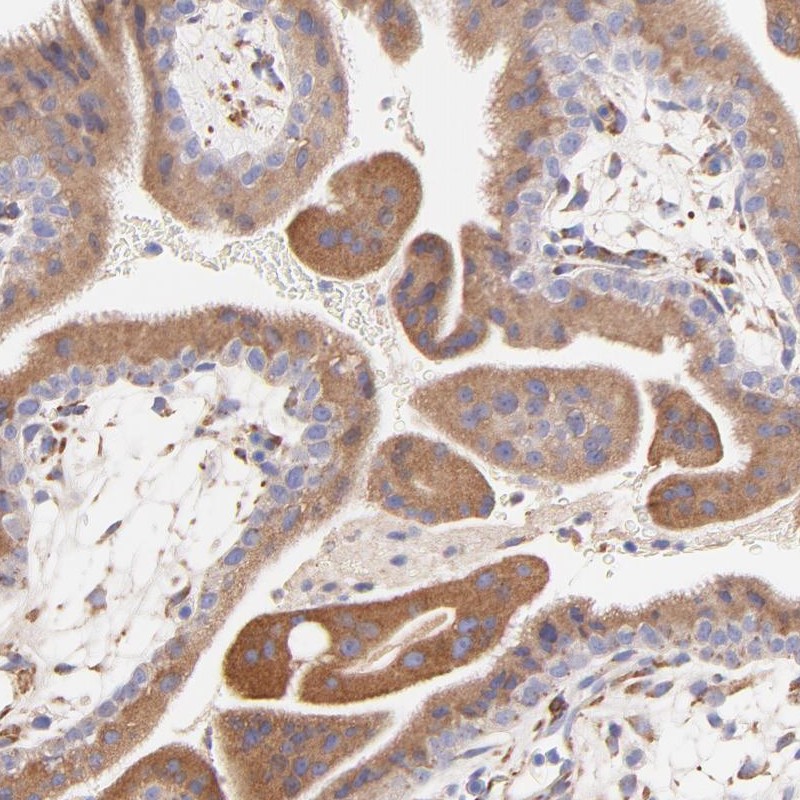

Immunohistochemistry is used for validating antibody reliability by assessing staining pattern in 44 normal tissues. Validation scores include Enhanced, Supported, Approved and Uncertain.

Results of validation by standard or enhanced validation based on assessment of antibody performance in 44 normal tissues.

Standard validation results in scores Supported, Approved or Uncertain. An image representative of the antibody staining pattern is shown.

Conformance of the expression pattern with available gene/protein characterization data in scientific literature and data from bioinformatic predictions.

Partly consistent with extensive gene/protein characterization data.

Consistent with extensive gene/protein characterization data.

Medium consistency between antibody staining and RNA expression data.